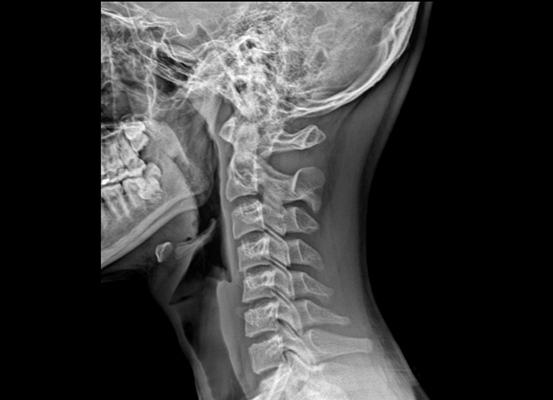

우선 목디스크란 목뼈 사이의 디스크가 깨지거나 상해 일어나는 질환을 의미합니다. 디스크는 척추뼈 사이에서 충격을 흡수하고 신경을 보호해주는 역할을 하는데, 디스크가 손상되면 신경이 압박되어 통증, 저림, 마비 등의 증상이 보여집니다.

우리의 목은 인체에서 무척 요긴한 역할을 합니다. 머리를 지지하여 돕고, 머리를 움직여 시야를 확보하는 역할을 히며, 척추의 시작 부분으로서 척추를 지켜주고, 척추를 통해 뇌와 인체의 다른 부분으로 신경을 보급하는 역할을 합니다.